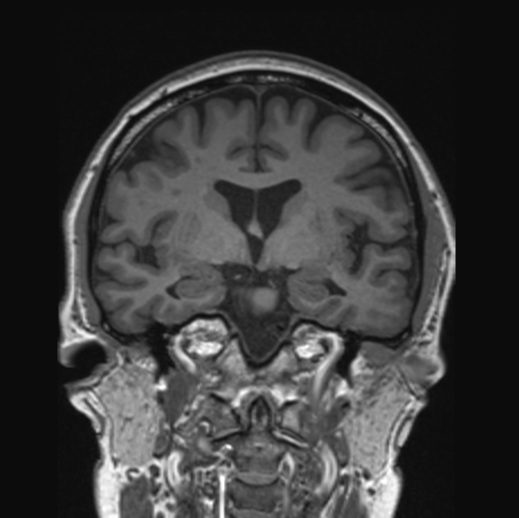

This imaging technique provides a non-invasive look inside the brain using powerful magnetic resonance technology. It is particularly beneficial for individuals with stroke risk factors.

RadLink’s diagnostic centres are equipped with modern MRI technology and are conveniently located across Singapore, including at Camden Medical. Our latest MRI scanner features a wide-bore opening that helps patients remain relaxed and feel less confined. Its patient-centric technology also offers patients the opportunity to watch a movie or film on an overhead mirror during the scan to help them relax and manage any discomfort. This helps patients overcome their fear of MRI and ensures a calm and seamless procedure.